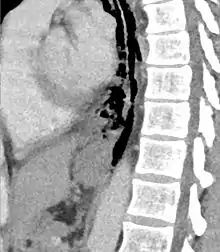

Sagittal reformatted CT image showing discontinutity in the wall of the posterolateral aspect of the distal esophagus

The diagnosis of Boerhaave's syndrome is suggested on the plain chest radiography and confirmed by chest CT scan. The initial plain chest radiograph is almost always abnormal in patients with Boerhaave's syndrome and usually reveals mediastinal or free peritoneal air as the initial radiologic manifestation. With cervical esophageal perforations, plain films of the neck show air in the soft tissues of the prevertebral space.

Hours to days later, pleural effusion(s) with or without pneumothorax, widened mediastinum, and subcutaneous emphysema is typically seen. CT scan may show esophageal wall edema and thickening, extraesophageal air, periesophageal fluid with or without gas bubbles, mediastinal widening, and air and fluid in the pleural spaces, retroperitoneum or lesser sac.